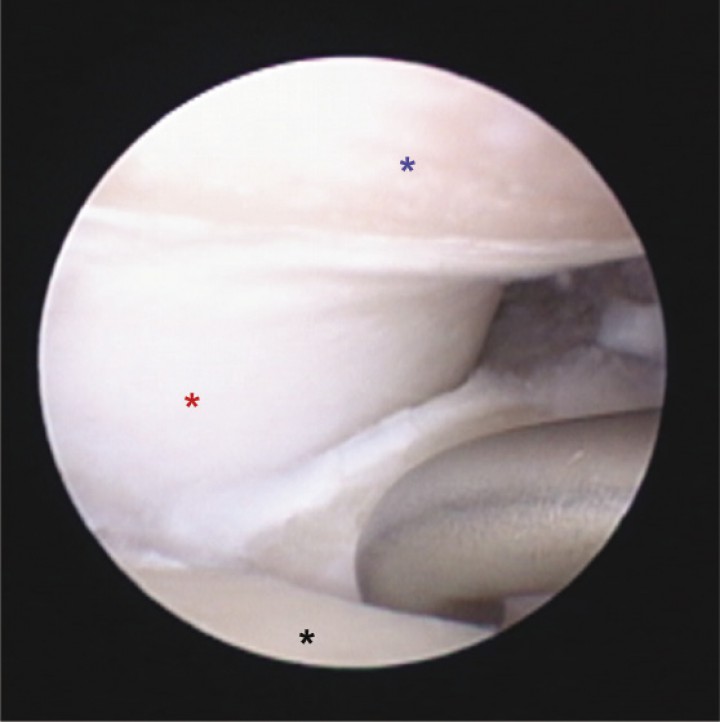

Este es un estudio clínico retrospectivo en el que se incluyen perros diagnosticados de ECM de codo mediante evaluación clínica, estudio radiográfico (Fig. 1), tomografía computarizada (Fig. 2) y evaluación artroscópica (Fig. 3). Dichos pacientes fueron intervenidos mediante la técnica quirúrgica PAUL (Fig. 4) tras la realización de una artroscopia de codo en el mismo acto quirúrgico. Los criterios de inclusión fueron los siguientes: perros que habían sido sometidos a dicho procedimiento quirúrgico en uno o ambos codos y que habían superado un periodo de evolución de cómo mínimo 4 meses. En el caso de intervenirse ambos codos, estas intervenciones debían haberse hecho en dos actos quirúrgicos independientes y con un intervalo mínimo entre ellos de 4 meses.

<p>Radiografía lateral (A) y cráneo-caudal (B) prequirúrgicas de un codo afectado de enfermedad del compartimento medial. Radiografía lateral (C) y cráneo-caudal (D) postquirúrgicas inmediatas; se aprecia la osteotomía y la colocación de la placa correctamente, observándose el desplazamiento del fragmento proximal producido por el implante.</p>

Radiografía lateral (A) y cráneo-caudal (B) prequirúrgicas de un codo afectado de enfermedad del compartimento medial. Radiografía lateral (C) y cráneo-caudal (D) postquirúrgicas inmediatas; se aprecia la osteotomía y la colocación de la placa correctamente, observándose el desplazamiento del fragmento proximal producido por el implante.

En primer lugar, mediante la artroscopia se realizaba el examen completo de la articulación: incisura cubital, cabeza del radio, cóndilos lateral y medial y coronoides lateral y medial (Fig. 3). En los casos en que existía un fragmento de coronoides medial, aislado o no, éste era extraído durante el procedimiento artroscópico. En las superficies en que se apreciaba condromalacia severa, erosiones o úlceras cartilaginosas (principalmente en coronoides medial), dichas zonas eran legradas y cureteadas hasta la aparición de zona de hueso subcondral sano, que se evidenciaba por la presencia de sangrado del mismo. Tras estudiar los signos de estrés en el compartimento medial (realizando los procedimientos necesarios y previamente expuestos vía artroscópica) y comprobar la integridad del compartimento lateral, se continuaba con la realización de la técnica quirúrgica PAUL. Para ello se realizaba un abordaje caudolateral al tercio proximal de la diáfisis cubital, para posteriormente realizar una osteotomía cubital y colocar una placa de sistema avanzado de bloqueo (ALPS, Kyon, Zurich) de 2 o 3 mm de escalón según las mediciones realizadas (Fig. 4). La medición se realizaba sobre la proyección radiológica cráneo-caudal, valorando el ángulo que formaba el eje longitudinal del radio con el eje de la articulación del codo. Según especifica el fabricante, si este ángulo es mayor de 82º se emplea un escalón de 2 mm y si es menor, de 3 mm.